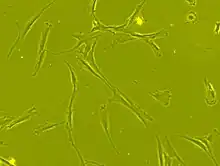

Stem cell transplantation is an important avenue for SCI research: the goal is to replace lost spinal cord cells, allow reconnection in broken neural circuits by regrowing axons, and to create an environment in the tissues that is favorable to growth.[50] A key avenue of SCI research is research on stem cells, which can differentiate into other types of cells—including those lost after SCI.[50] Types of cells being researched for use in SCI include embryonic stem cells, neural stem cells, mesenchymal stem cells, olfactory ensheathing cells, Schwann cells, activated macrophages, and induced pluripotent stem cells.[163] Hundreds of stem cell studies have been done in humans, with promising but inconclusive results.[150] An ongoing Phase 2 trial in 2016 presented data[164] showing that after 90 days, 2 out of 4 subjects had already improved two motor levels and had thus already achieved its endpoint of 2/5 patients improving two levels within 6–12 months. Six-month data is expected in January 2017.[165]